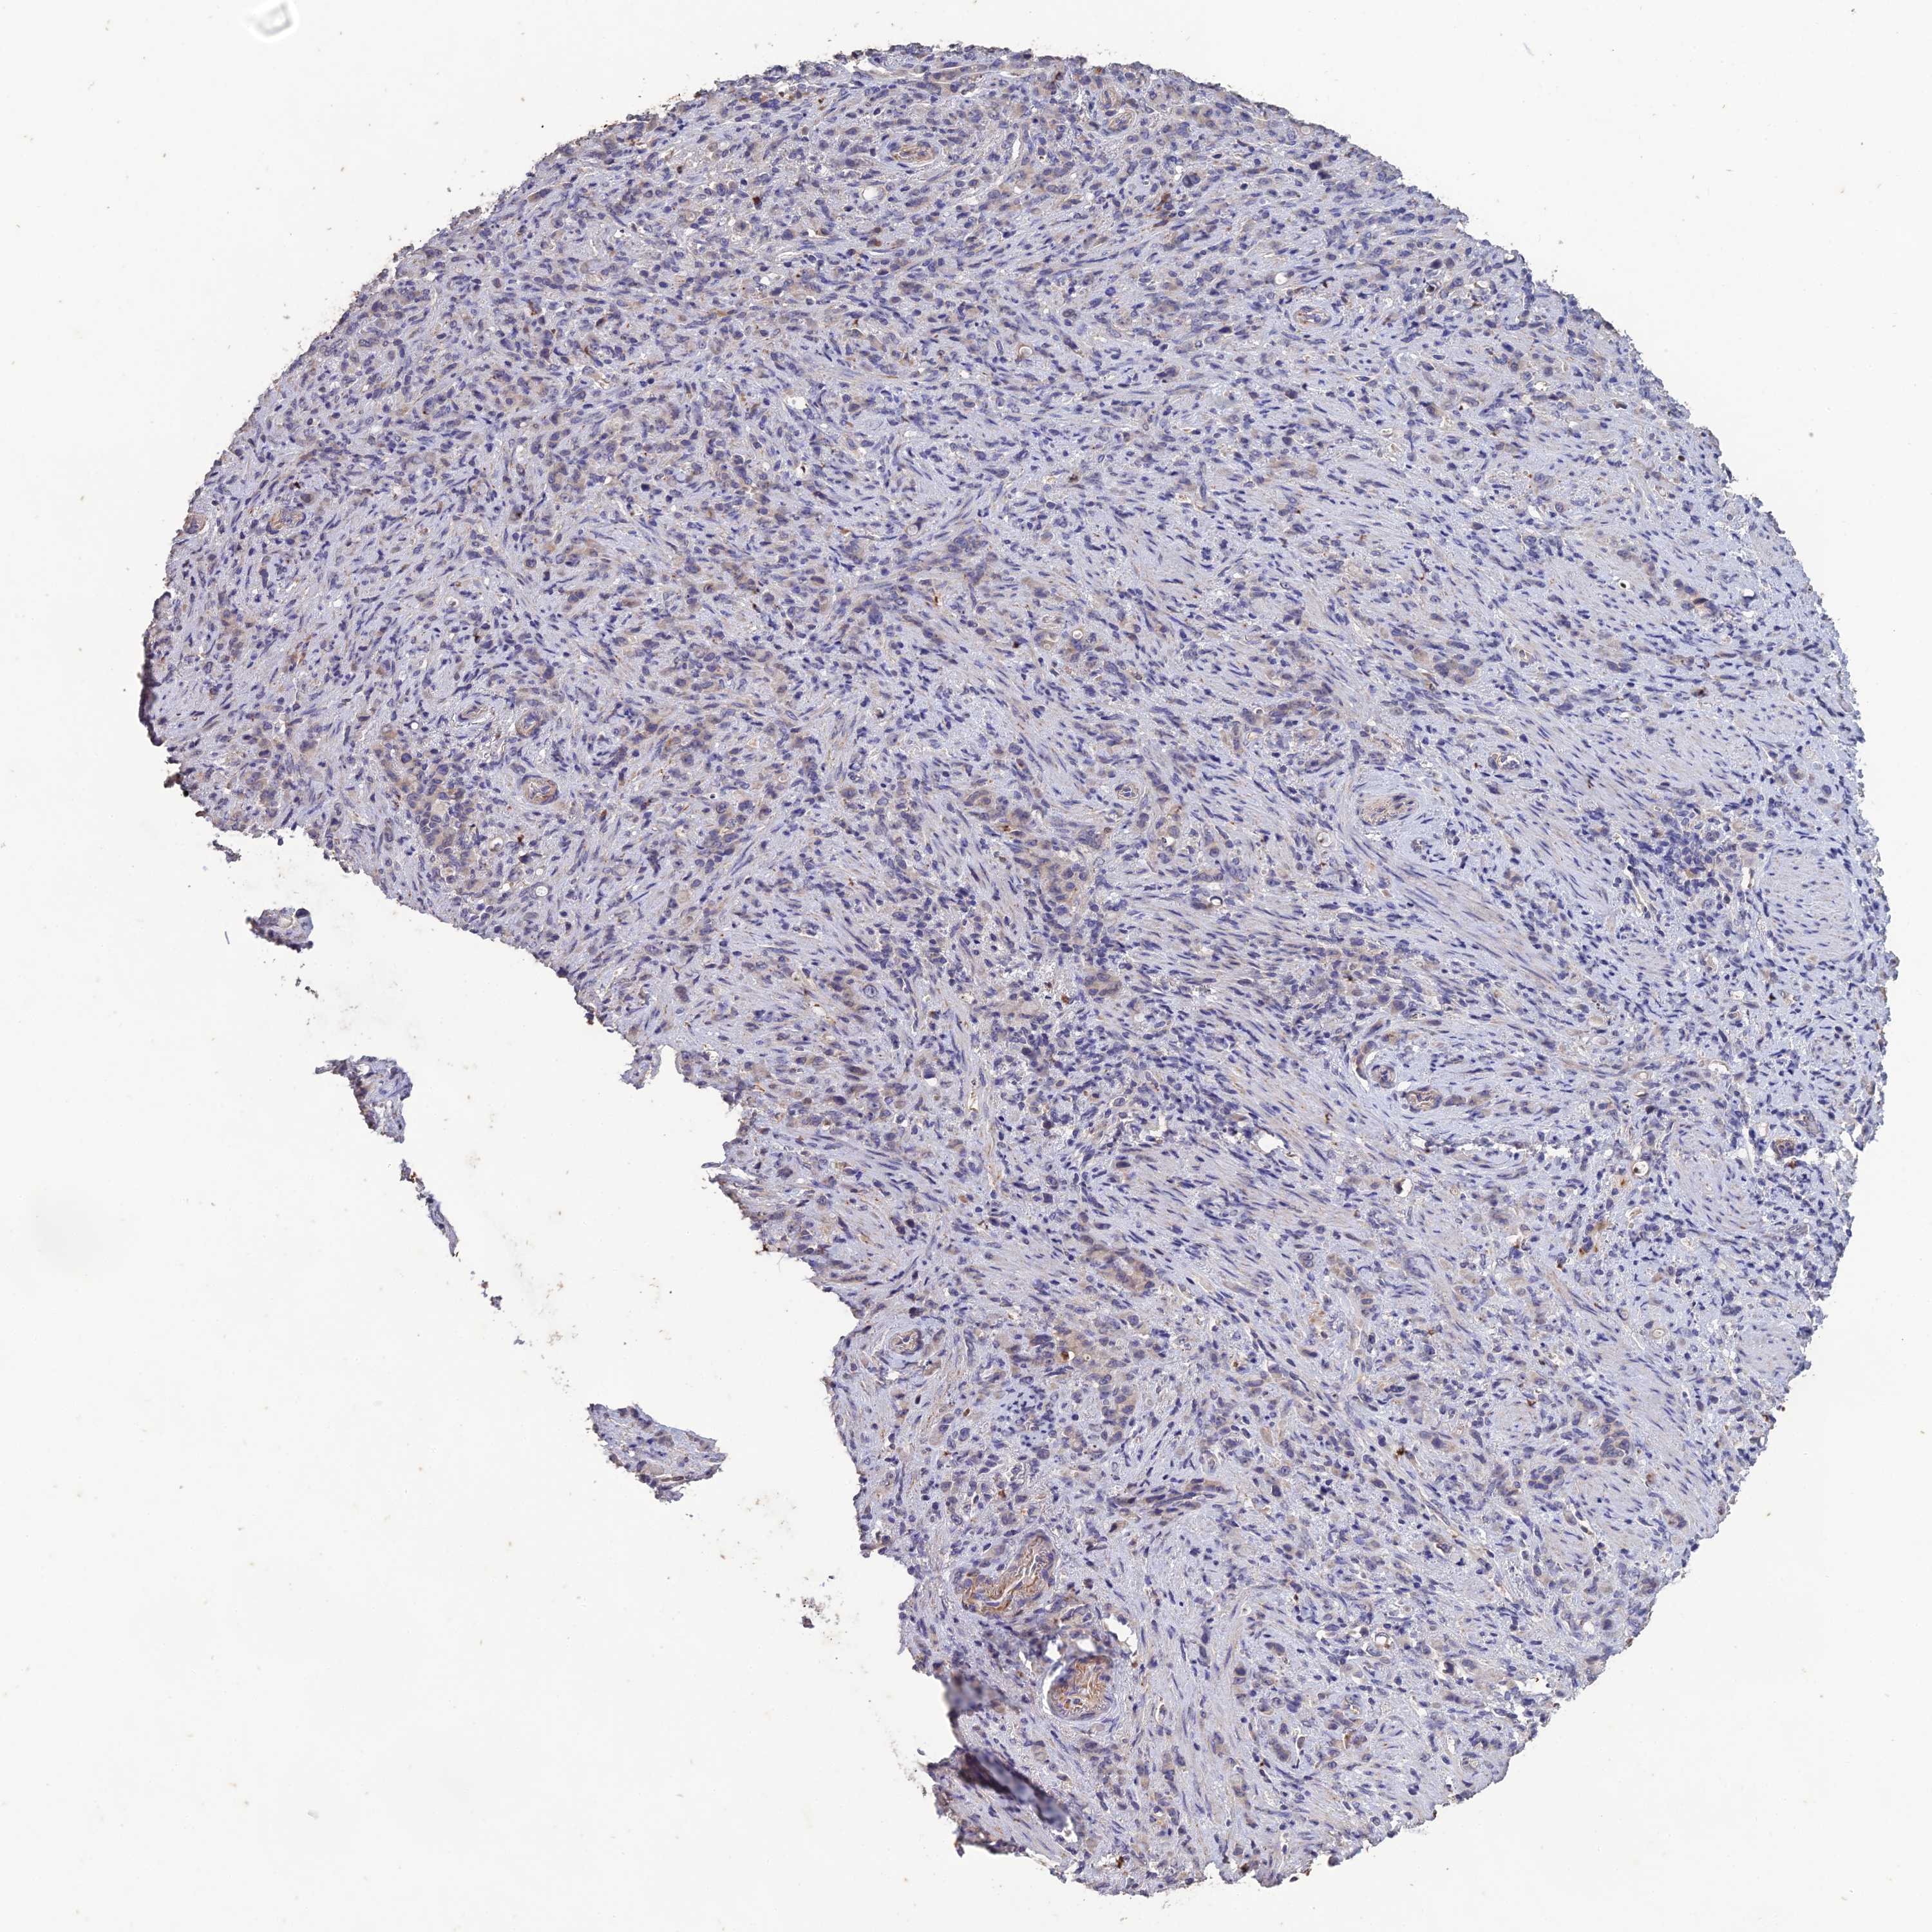

STOMACH CANCER - Protein expressioni

A mouse-over function shows sample information and annotation data. Click on an image to view it in a full screen mode. Samples can be filtered based on level of antibody staining by selecting one or several of the following categories: high, medium, low and not detected. The assay and annotation is described here.

Note that samples used for immunohistochemistry by the Human Protein Atlas do not correspond to samples in the TCGA dataset.

Antibody stainingi

Antibody staining in the annotated cell types in the current human tissue is reported as not detected, low, medium, or high, based on conventional immunohistochemistry profiling in selected tissues. This score is based on the combination of the staining intensity and fraction of stained cells.

Each image is clickable and will lead to virtual microscopy that enables deeper exploration of all samples and also displays staining intensity scores, fraction scores and subcellular localization as well as patient and tissue information for each sample.

Antibody HPA043971

Staining

High

Medium

Low

Not detected

Intensity

Strong

Moderate

Weak

Negative

Quantity

>75%

75%-25%

<25%

None

Location

Nuclear

Cytoplasmic/membranous

Cytoplasmic/membranous,nuclear

Adenocarcinoma, NOS